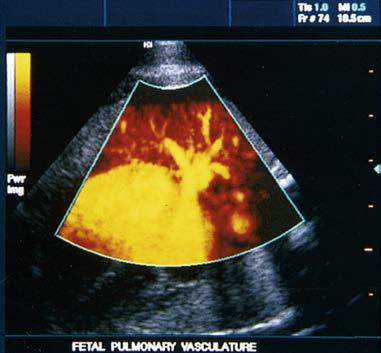

enable color-coded 2D and 3D presentations of Doppler information (color-Doppler displays) to be superimposed on gray-scale anatomic images (Figure 1-13). Doppler information is applied to loudspeakers for audible evaluation and to spectral-Doppler displays for quantitative analysis (Figure 1-14). The spectral-Doppler operation includes

anatomic imaging to determine the location(s) from which the spectral information is acquired (Figure 1-15).

Doppler information is presented in audible, colorDoppler, and spectral-Doppler forms.

FIGURE 1-13 Color-Doppler displays of blood flow. Presented in forms called (A) colorDoppler shift, (B) color-Doppler power, and (C) three-dimensional color-Doppler power displays.